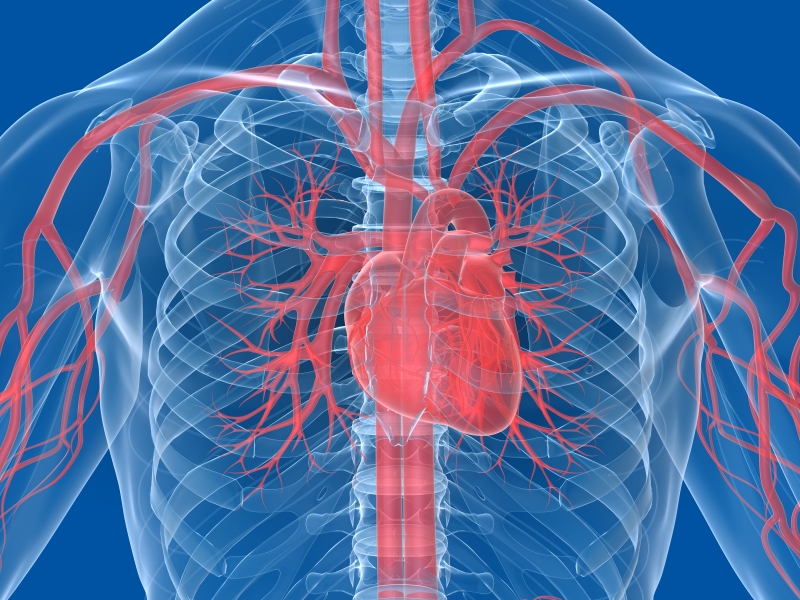

Hjertet har form som en kjegle med spissen (apeks) ned og den brede delen, bunnen (basis) opp. Hjertet er pakket inn i hjerteposen, som kalles perikard. Perikardet består av to lag.

Hjertet har 4 hjertekamre

Hjertet består av fire hjertekamre. Forkamrene (atriene) og hjertekamrene (ventriklene)

- Høyre forkammer

- Venstre forkammer

- Høyre hjertekammer

- Venstre hjertekammer

Blodet flommer alltid kun èn vei gjennom hjertet

Før vi går videre er det viktig å huske på at blodet alltid flommer i samme retning gjennom hjertet. Rekkefølgen er slik:

- Fra den store venen Venae Cava og inn i høyre atrie

- Fra høyre atrie til høyre ventrikkel

- Fra høyre ventrikkel, via lungene til venstre atrie

- Fra venstre atrie til venstre ventrikkel

- Fra venstre ventrikkel til hovedpulsåren, aorta.